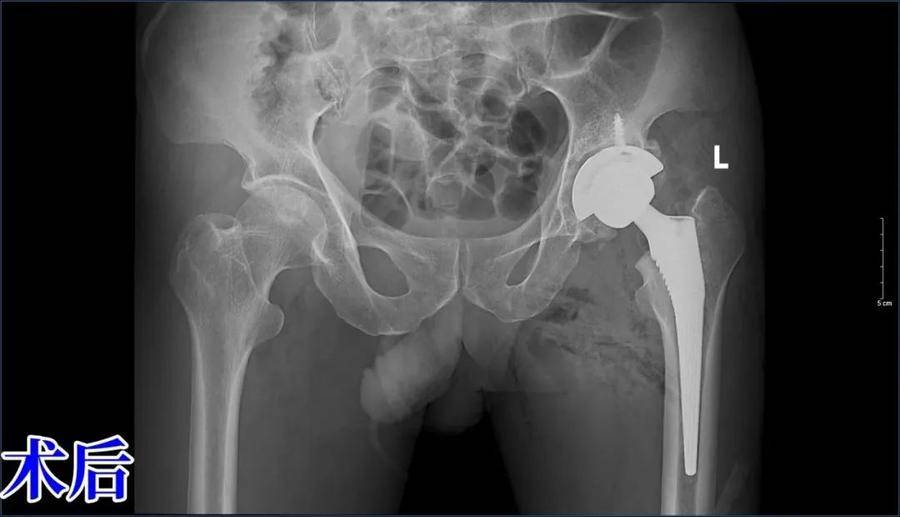

经过完善的术前准备,在手术室团队及麻醉科的密切配合下,由孙焕科主任主刀成功实施了左侧全髋关节置换+内收肌松解术。术后,患者恢复情况良好,不仅疼痛得到了极大缓解,左下肢的活动能力也有了显著提高。